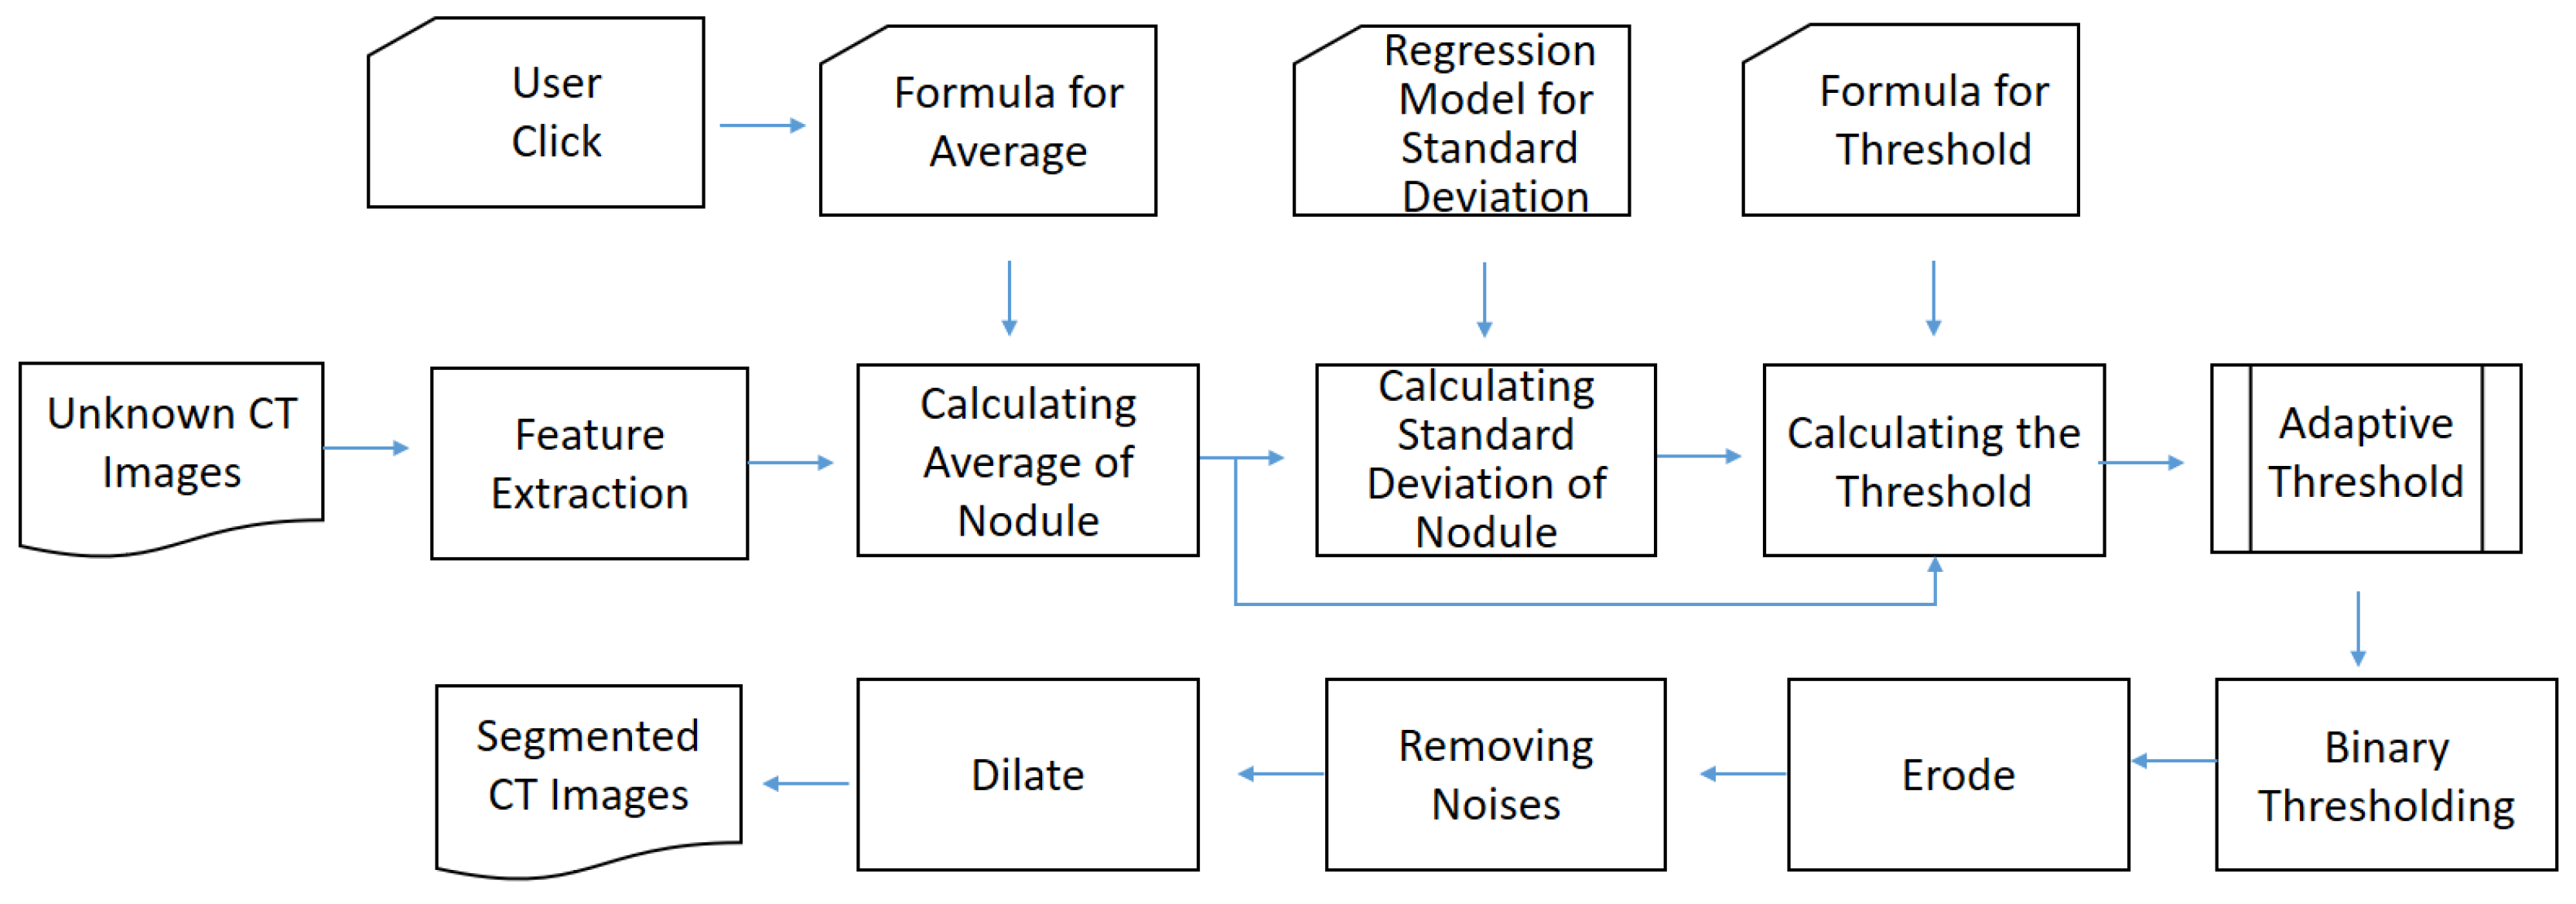

- Offline preprocessing: In this stage, lungs are partitioned from the known computed tomography (CT) images first. Next, the necessary components are generated for online recognition, including adaptive threshold, the anchor-fixed Mask-RCNN model, and invasiveness recognition model. For the adaptive threshold, it is determined by two statistical regressions. For Mask-RCNN, it is trained with a fixed anchor. For the invasiveness recognition model, the features are extracted and filtered first. Then, a set of balanced classification models is trained by equalized down-sampling.

- II.

- Online recognition: If the offline preprocessing is completed, the online recognition starts with a submission of unknown CT images. Next, the user will click the target nodules. Then, the system attempts to segment the nodules from unknown images by thresholding. If the result is null, the segmentation will be finished by Mask-RCNN. Finally, based on the segmented nodules, the invasiveness will be recognized by the boosting an ensemble classification model called BEED.

Determining the Threshold Formula

Thresholding-Based Morphology for Semi-Automated Segmentation